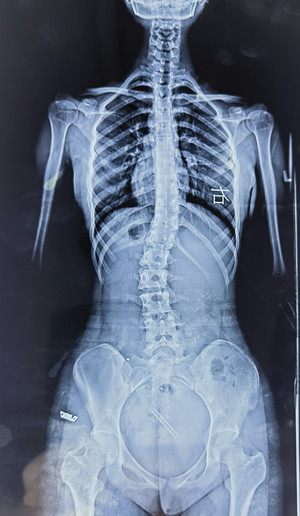

脊柱側(cè)彎拍X片

我的孩子可能脊柱側(cè)彎了,想拍一個 “ 站立式全脊柱正側(cè)位X片 ” 。

您也可以給醫(yī)生看上圖,問下醫(yī)生能不能拍這樣的X片(并不是所有醫(yī)院都有能力拍這樣的X片)。